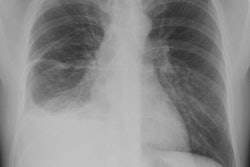

X-ray:

The lesion typically presents with a pleural effusion with associated smooth, nodular pleural thickening (resembling a mesothelioma).